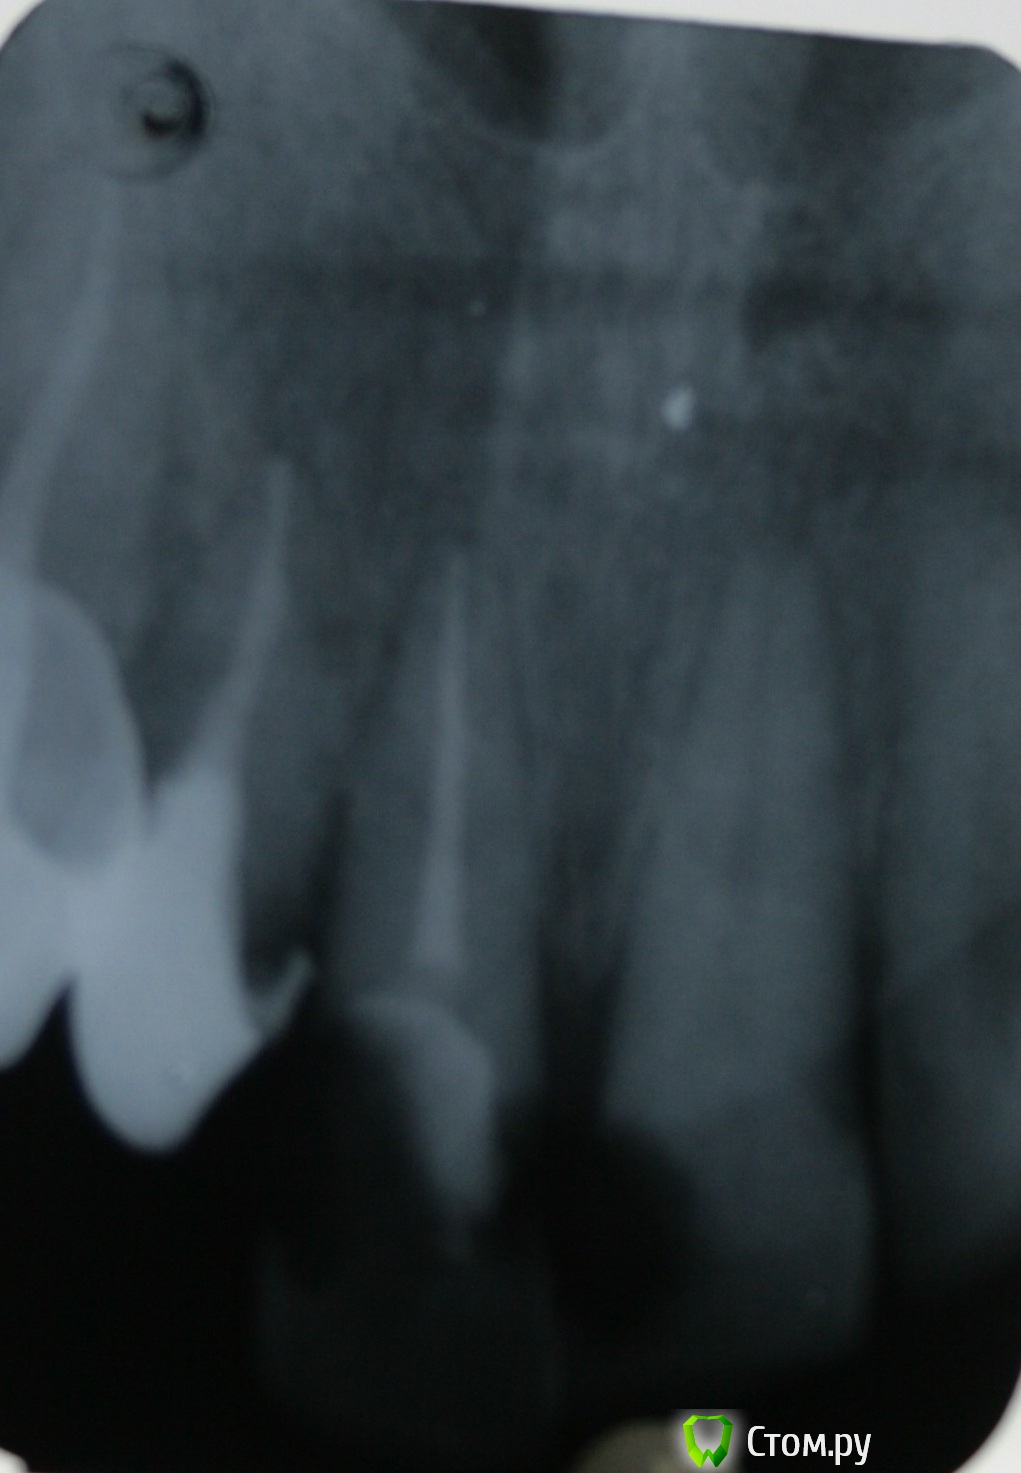

St. Опубликовано 7 ноября, 2014 Автор Поделиться Опубликовано 7 ноября, 2014 Вот ещё. Тут вроде симпатично вышло. Жалобы на боли при накусывании. Перкуссия +++. Термопроба -.Зуб на половину состоит из пломбы. лечен со слов несколько лет назад. Симптоматический апикальный периодонтит 21.Ковровая дорожка. ПроТейпры до ф1. Апикально 50.02. Гипохлорит, перекись, хлоргексидин, эдта. Пломбировка Латералкой. Думала триоксидентом сперва, но получила хороший апмкальный упор и канал высушился без проблем. Поэтому гутта. 6 Ссылка на комментарий

Гарриевич Опубликовано 9 ноября, 2014 Поделиться Опубликовано 9 ноября, 2014 Поэтому гутта.классная латералька ) Ссылка на комментарий

St. Опубликовано 9 ноября, 2014 Автор Поделиться Опубликовано 9 ноября, 2014 классная латералька )Спасибо! Ссылка на комментарий